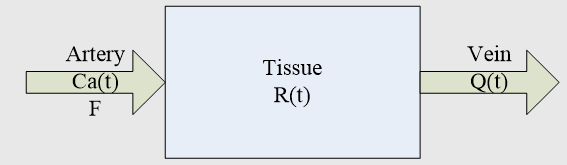

1、脑部

a、脑部灌注增强造影

脑部的生理性功能活动以及病理活动与组织血流微循环状态密切相关。

脑部灌注增强造影对脑部组织生理、病理变化非常敏感。

可了解血液动力学及功能上的变化。

可比CT平扫等常规影像技术更早更准确地诊断脑组织缺血等疾病。

灌注成像的理论基础

核医学放射性示踪剂稀释理论以及中心容积定律:

血容量=血流量×平均通过时间

通过直接测量CT值随时间的变化曲线获得组织内碘对比剂浓度随时间变化的曲线(Time-Density Curve, TDC),从而获得:

脑血流量(Cerebral Blood Flow, CBF)

脑血容量(Cerebral Blood Volume, CBV)

平均通过时间(Mean Transit Time, MTT)

达峰时间(Time TO Peak, TTP)

灌注图像后处理算法

最大斜率法

最大斜率法把器官或组织看作一个“黑箱”,示踪剂经由一条动脉进入“黑箱”,然后快速渗透到毛细血管和细胞外间质中,经过很短的一段时间后开始从一条静脉随血流流出。

组织中的对比剂总量等于流入的对比剂总量减去流出的对比剂总量。

去卷积法

模型原理:

房室模型的一种,研究器官或组织的系统响应函数。对理想状态下,瞬时注射单位质量的示踪剂产生的组织增强曲线,即组织的脉冲响应函数(IRF)进行处理。脉冲响应函数反映了物质在组织中随着时间的分布情况 。

灌注图像后处理结果

CT脑灌注分析参数结果伪彩图(CBF,CBV,MTT,TTP)

MR灌注分析参数结果伪彩图(CBF,CBV,MTT,TTP)